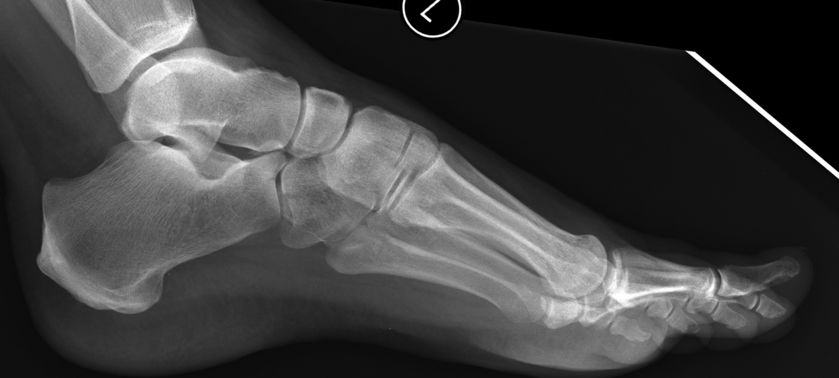

En sık kırılan ayak kemiğidir

Kırıklar eklem içi ve eklem dışı olarak gruplanır.

Sıklıkla yüksekten düşme sonucu gözlenirler.